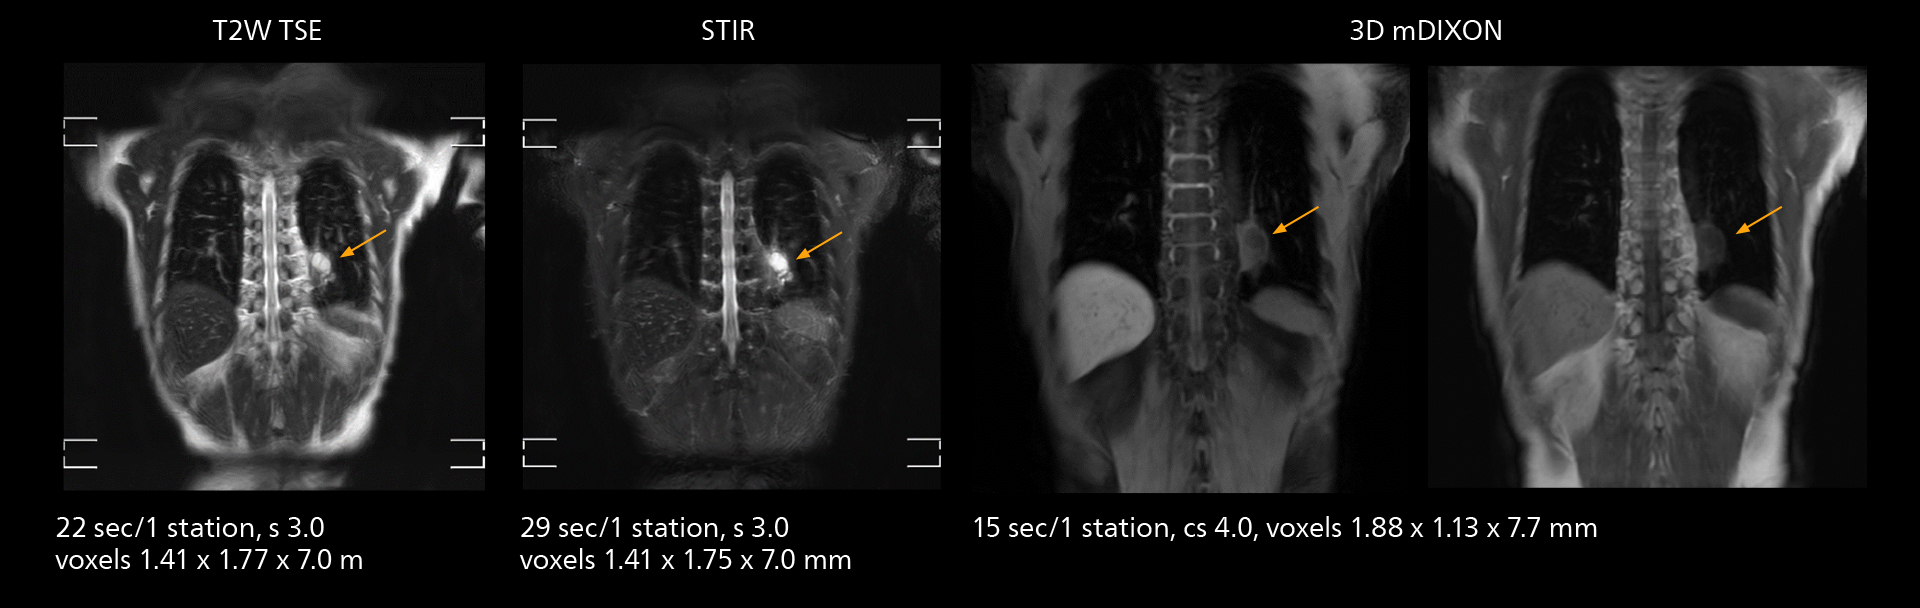

The value of the Elition X gradients is also evident in DWIBS studies. “The fact that we can consistently obtain distortion‐free DWIBS while reducing imaging time at three coronal stations is excellent,” Dr. Makuuchi says. “In these patients, it’s also important that the application of Compressed SENSE to T2‐weighted, STIR and mDIXON sequences has no impact on the examination time of whole‐body imaging. As a result of the increased speed and higher image quality we realize, DWIBS studies have now become routine examinations.”

Fast whole body DWIBS examination

With SmartPath to Elition X the team can obtain excellent quality DWIBS imaging and reduce imaging time. Other sequences also fit in the examination slot. This case shows left paravertebral neurogenic tumor and Th10 vertebral hemangiomas.